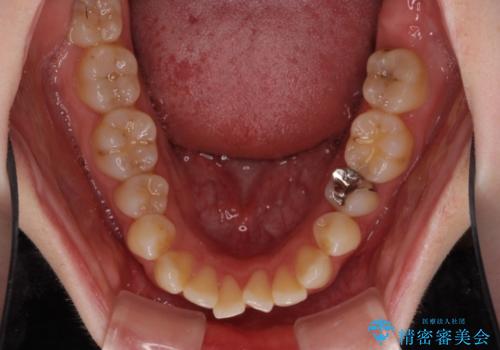

- 前歯のデコボコを気にして来院された患者様です。

下顎が骨格的にずれており、上下正中を合わせることは難しいことが予想されたため、デコボコの解消を主目的として、ワイヤー矯正を行うこととしました。